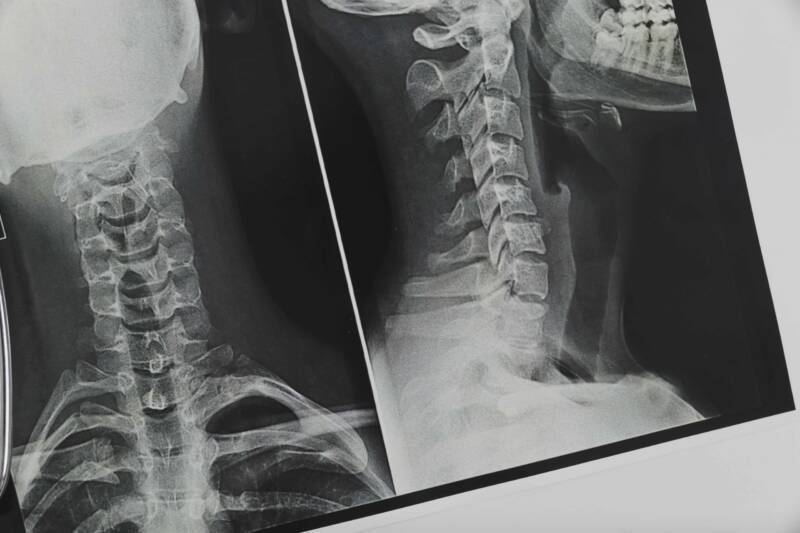

*🎴सावंतवाडी, दि-११*:-सावंतवाडी उपजिल्हा रुग्णालयातील एक्स-रे विभाग गेल्या दोन वर्षांपासून एकाच कर्मचाऱ्यावर अवलंबून असल्याने रुग्णांना एक्स- रेसाठी ताटकळत बसावे लागत आहे. एक्स-रेसाठी रुग्णसंख्या वाढत असल्याने कार्यरत असलेल्या कर्मचाऱ्यावर कामाचा अतिरिक्त ताण पडत असताना आरोग्य प्रशासन दखल घेत नाही.सावंतवाडी उपजिल्हा रुग्णालयातील समस्यांबाबत लोकप्रतिनिधींनी गांभीर्याने लक्ष देणे गरजेचे आहे. उपजिल्हा रुग्णालयातील एक्स-रे विभागासाठी किमान तीन कर्मचाऱ्यांची गरज आहे. एक कर्मचारी सेवानिवृत्त झाल्यानंतर एकाच कर्मचाऱ्यावर एक्स-रे विभाग अवलंबून आहे. एका रुग्णाचा एक्स-रे काढण्यासाठी नावनोंदणीपासून ते एक्स-रे देईपर्यंत किमान पंधरा मिनिटे लागतात. एका दिवसात ३० ते ३५ जणांचा एक्सरे काढण्यासाठी कार्यरत कर्मचाऱ्यावर ताण पडत आहे. त्यात रुग्णांच्या नातेवाईकांकडून होणाऱ्या उद्धट वर्तनाचा सामनाही करावा लागत आहे. चार दिवसांपूर्वी माजगाव येथे झालेल्या अपघातातील जखमींचे एक्स-रे कार्यरत असलेल्या कर्मचाऱ्याने सायंकाळी उशिरापर्यंत काढून सेवा दिली. तरीही नाहक रोषाला त्याला सामोरे जावे लागले. एक्स-रे विभागात किमान तीन कर्मचारी नियुक्ती आवश्यक आहे. पावसाळ्यात आजाराच्या उद्भवणाऱ्या पार्श्वभूमीवर प्रशासनाने एक्स-रे विभागात कायमस्वरुपी तीन कर्मचाऱ्यांची नियुक्ती करावी, अशी मागणी केली जात आहे.